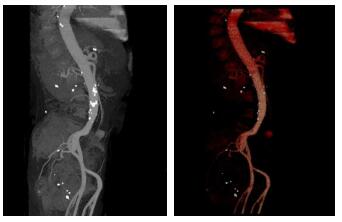

1 资料与方法男性患者, 63岁, 因“腰痛2个月, 突发腹痛3 h”于2018年12月28日收入本院急诊抢救室。患者腰背痛病史2个月, 曾在本院骨科门诊就诊。查体腰背有轻度叩痛, 弯腰活动有受限。神经系统查体阴性。本院CT检查示, 腰4椎体上缘局部骨质吸收、破坏, 椎旁软组织稍肿胀, 考虑感染性炎症可能(图 1A)。复查腰椎MRI示, 腰4椎体上缘局部骨质破坏, 腰3/4椎体斑片状骨髓水肿, 椎旁软组织水肿。提示腰3/4感染性脊柱炎(图 1B)。患者血沉及CRP升高, 诊断为腰椎感染。患者曾在当地医院进行治疗, 包括卧床休息、抗感染治疗。

| 图 1 患者骨科门诊就诊影像学结果(A: CT示腰4椎体上缘局部骨质吸收、破坏, 椎旁软组织稍肿胀; B:MRI示腰4椎体上缘局部骨质破坏, 腰3/4椎体斑片状骨髓水肿, 椎旁软组织水肿) |